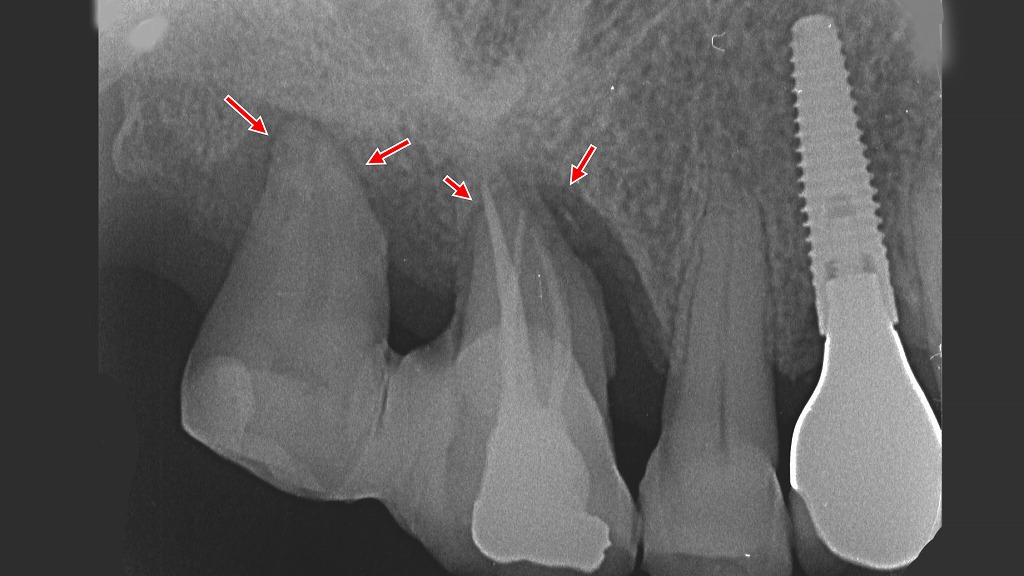

プラークが進行させた重度歯周病|6・7番の歯槽骨吸収と治療選択

レントゲン画像では、プラークの長期的な付着と歯周病の進行により、6・7番周囲の歯槽骨が根尖付近まで大きく吸収していることが確認できます。この状態では歯の保存は困難で、抜歯が適応となります。一方、4番部位は歯を失った後の咬合回復としてインプラント治療が行われています。プラークコントロールを怠ると、歯周病はここまで進行する可能性があり、早期の予防と治療が極めて重要です。